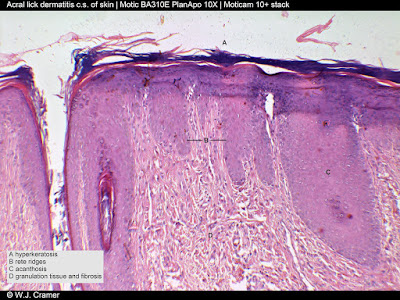

Indicated on the microscopic images:

B - RETE RIDGES: These are epithelial protrusions into the underlying connective tissue.

C - ACANTHOSIS OR ACANTHOSIS NIGRICANS: Increase in the number of cell layers in the epidermis, with a black discoloration as can be seen in the specimen.

D - GRANULATION TISSUE* & FIBROSIS*: The dermis is thickened by granulation tissue and fibrosis.

* Hyperkeratosis: Thickening of the top layer of the skin

** Granulation tissue: New tissue formed during the healing process of a wound

*** Fibrosis: Formation of excess fibrous connective tissue